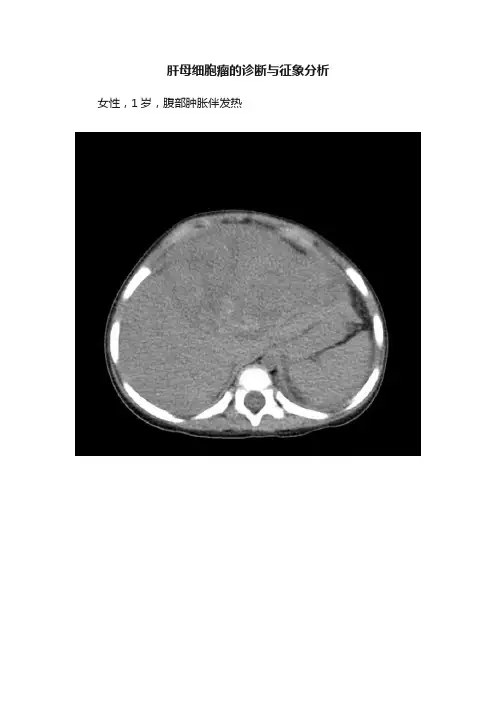

肝母细胞瘤的诊断与征象分析女性,1岁,腹部肿胀伴发热影像学表现肝左右叶交界处可见一略低于肝实质密度的巨大病灶,内部密度不均匀,可见混杂高低密度区;增强扫描病灶呈不均匀强化;病灶突出于肝包膜生长,肝周见少量液体密度影,腹腔脏器受压移位。

诊断肝母细胞瘤鉴别诊断1 .原发性肝细胞癌:CT 也表现为肝内低密度灶,少数含点状钙化,AFP 50 % 阳性,但肿块形态不规则、边缘模糊;缺少包膜,瘤旁常见大小不等的子灶。

肿瘤以外的肝脏可有脂肪肝、肝硬变等表现。

年龄以3 岁以上多见,不同于本病。

2 .肝横纹肌肉瘤:肿瘤边缘较清楚,可位于肝门区或左右肝内,呈不均匀低密度占位,出血坏死少见,罕有钙化,发病年龄约5 ~ 11 岁。

AFP 阴性有助于鉴别。

3 .肝转移瘤:年幼儿主要与神经母细胞瘤肝转移鉴别,后者可表现为大块结节融合灶侵占大面积肝实质,含多种形态钙化与本病相似。

其他如肾母细胞瘤、淋巴肉瘤等常为多发或单发结节灶,关键在于发现原发灶;淋巴肉瘤、神经母细胞瘤常可见腹部淋巴结肿大有别于本病。

讨论肝母细胞瘤为小儿最常见的肝脏胚胎性恶性肿瘤。

51% ~ 56% 多发生于3 岁以下,男发病率较女高,通常累积肝脏右叶。

肿瘤以单发巨块型为主,结节及弥漫性罕见。

鉴于肝母细胞瘤生长方式分为内生型和外生型。

多种形态继之分为单块型、结节型融合型、多结节型、弥漫型和囊肿型。

临床表现早期多以肝肿大和肝区疼痛为最初症状,进展期会出现上腹部或全腹膨隆、恶心呕吐、食欲不振、体重减轻、腹痛、腹泻、腹壁静脉曲张、发热、黄疸等表现,晚期出现腹水,多数病例肝功能正常,80% ~ 90%甲胎蛋白测定阳性,是最有意义的生化检查指标。

影像学表现HB 一般多发于肝右叶,其次为左右叶同时累及,单独发生在肝左叶较少见。

HB 通常表现为巨大的单一肿块,表现为多结节融合较少见。

大部分肿块边界清晰,有假包膜形成。

CT平扫肿块内密度不均匀,呈低、等混杂密度,较正常肝实质低,肿块内可见裂隙状或不规则片状密度更低区,肿块低密度区的周边表现为多个大小不等结节状相对稍高密度区。